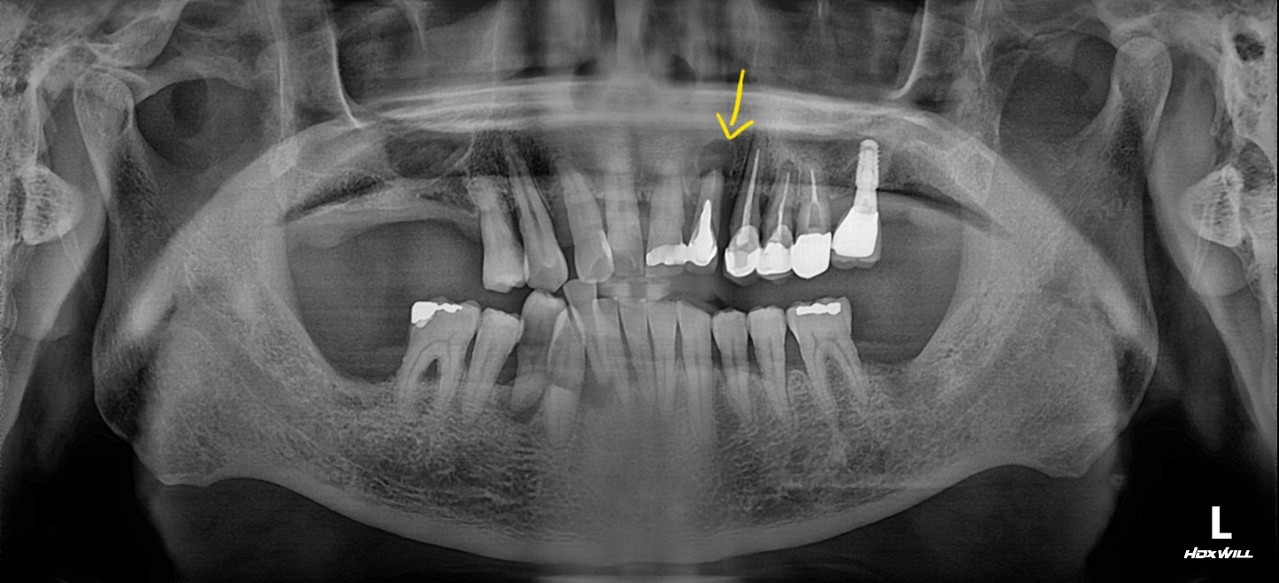

3단계

치수염 (신경까지 감염)

치아 신경까지 세균이 침범하여 심한 통증 발생

신경치료(근관치료) 후 크라운 씌움

본원에서는 올세라믹, 지르코니아 크라운 제작 후 당일 완성 가능